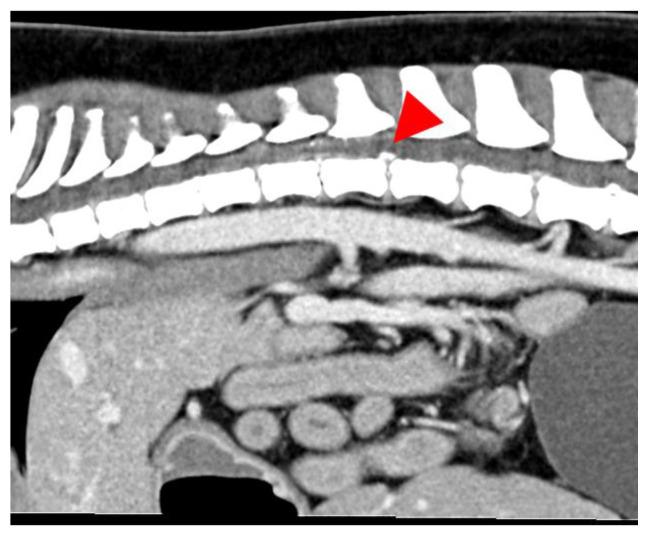

This retrospective study aims to investigate whether dogs with a contusive and dogs with a compressive intervertebral disc disease share comparable outcomes and prognoses when presenting with the same neurological grade. A total of 50 dogs with IVDE (compression group) and 45 dogs with ANNPE (contusion group) were included in this study. The protocol involved a thorough review of the medical records and CT/MRI images of the included dogs. Data encompassing signalment, initial clinical signs, post-diagnosis treatment and short-term outcomes (less than 8 months) were collected from the patient records. Information on long-term outcomes (more than 8 months) was obtained through interviews with the owners. Dogs in the compression group displayed clinical signs at a statistically significant younger age and were more likely to experience deteriorating neurological deficits compared to the contusion group. Conversely, dogs with contusions had a significantly higher incidence of external trauma history and vocalization at the onset of clinical signs. In both groups, the most affected spinal cord segment was T3-L3. The overall recovery rate to regain independent ambulation was 71% in the contusion group vs. 80% in the compression group. While some of the examined parameters revealed differences, most did not significantly differ between the groups.

这项回顾性研究旨在调查患有压迫性和挫伤性椎间盘疾病的犬只在呈现相同神经学分级时是否具有相似的结果和预后。本研究共纳入了50只患有椎间盘突出症(压迫组)的犬只和45只患有急性非化脓性神经炎(挫伤组)的犬只。该方案包括对纳入犬只的病历和CT/MRI图像进行全面审查。从患者记录中收集了包括信号特征、初始临床症状、诊断后治疗和短期结果(少于8个月)的数据。通过与犬主访谈获得了长期结果(超过8个月)的信息相较挫伤组,压迫组的犬只在统计学上更年轻的时候就出现了临床症状,并且更有可能出现神经功能缺损恶化的情况。相反,患有挫伤的犬只在临床症状出现时,有外部创伤史和发声的发生率显著更高。在两组中,受影响最严重的脊髓节段均为T3-L3。挫伤组恢复独立行走的总体恢复率为71%,而压迫组为80%。虽然一些检查参数显示出差异,但大多数参数在两组之间并无显著差异。